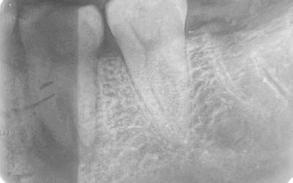

Paciente masculino de 29 años de edad, sin antecedentes médicos de interés acude al servicio de Cirugía Maxilofacial, el cual acude a la con sulta por odontalgía asociado al pri mer molar inferior izquierdo (Figura 1). Realizamos estudios radiográficos de dicho órgano (Figura 2), siendo valorado por especialista en prótesis y endodoncia quienes refieren no ser candidato para rehabilitación y tra tamiento de conductos con un pro nóstico poco favorable. Motivo por el cual se ofrece la opción de realizar TD del tercer molar inferior izquierdo al lecho quirúrgico del primer molar

Figura 2. Radiografía dentoalveolar inicial. Trasplante dental de terceros molares